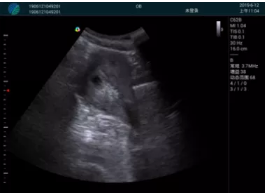

甲狀腺囊性結(jié)節(jié),囊壁鈣化,透聲好

甲狀腺囊性占位

2001年美國健康護(hù)理研究和質(zhì)量監(jiān)督局(AHRQ)批準(zhǔn)了一項(xiàng)關(guān)于提高患者安全性的報(bào)告,建議:在頸內(nèi)靜脈中心置管術(shù)時(shí)使用超聲引導(dǎo)。此后超聲引導(dǎo)穿刺被用于幾乎所有的急診穿刺操作,尤其是血管穿刺。

便攜超聲在急診穿刺中的應(yīng)用:

* 提高了穿刺成功率

* 減少了穿刺損傷及并發(fā)癥

* 縮短了操作時(shí)間

* 減輕了患者痛苦